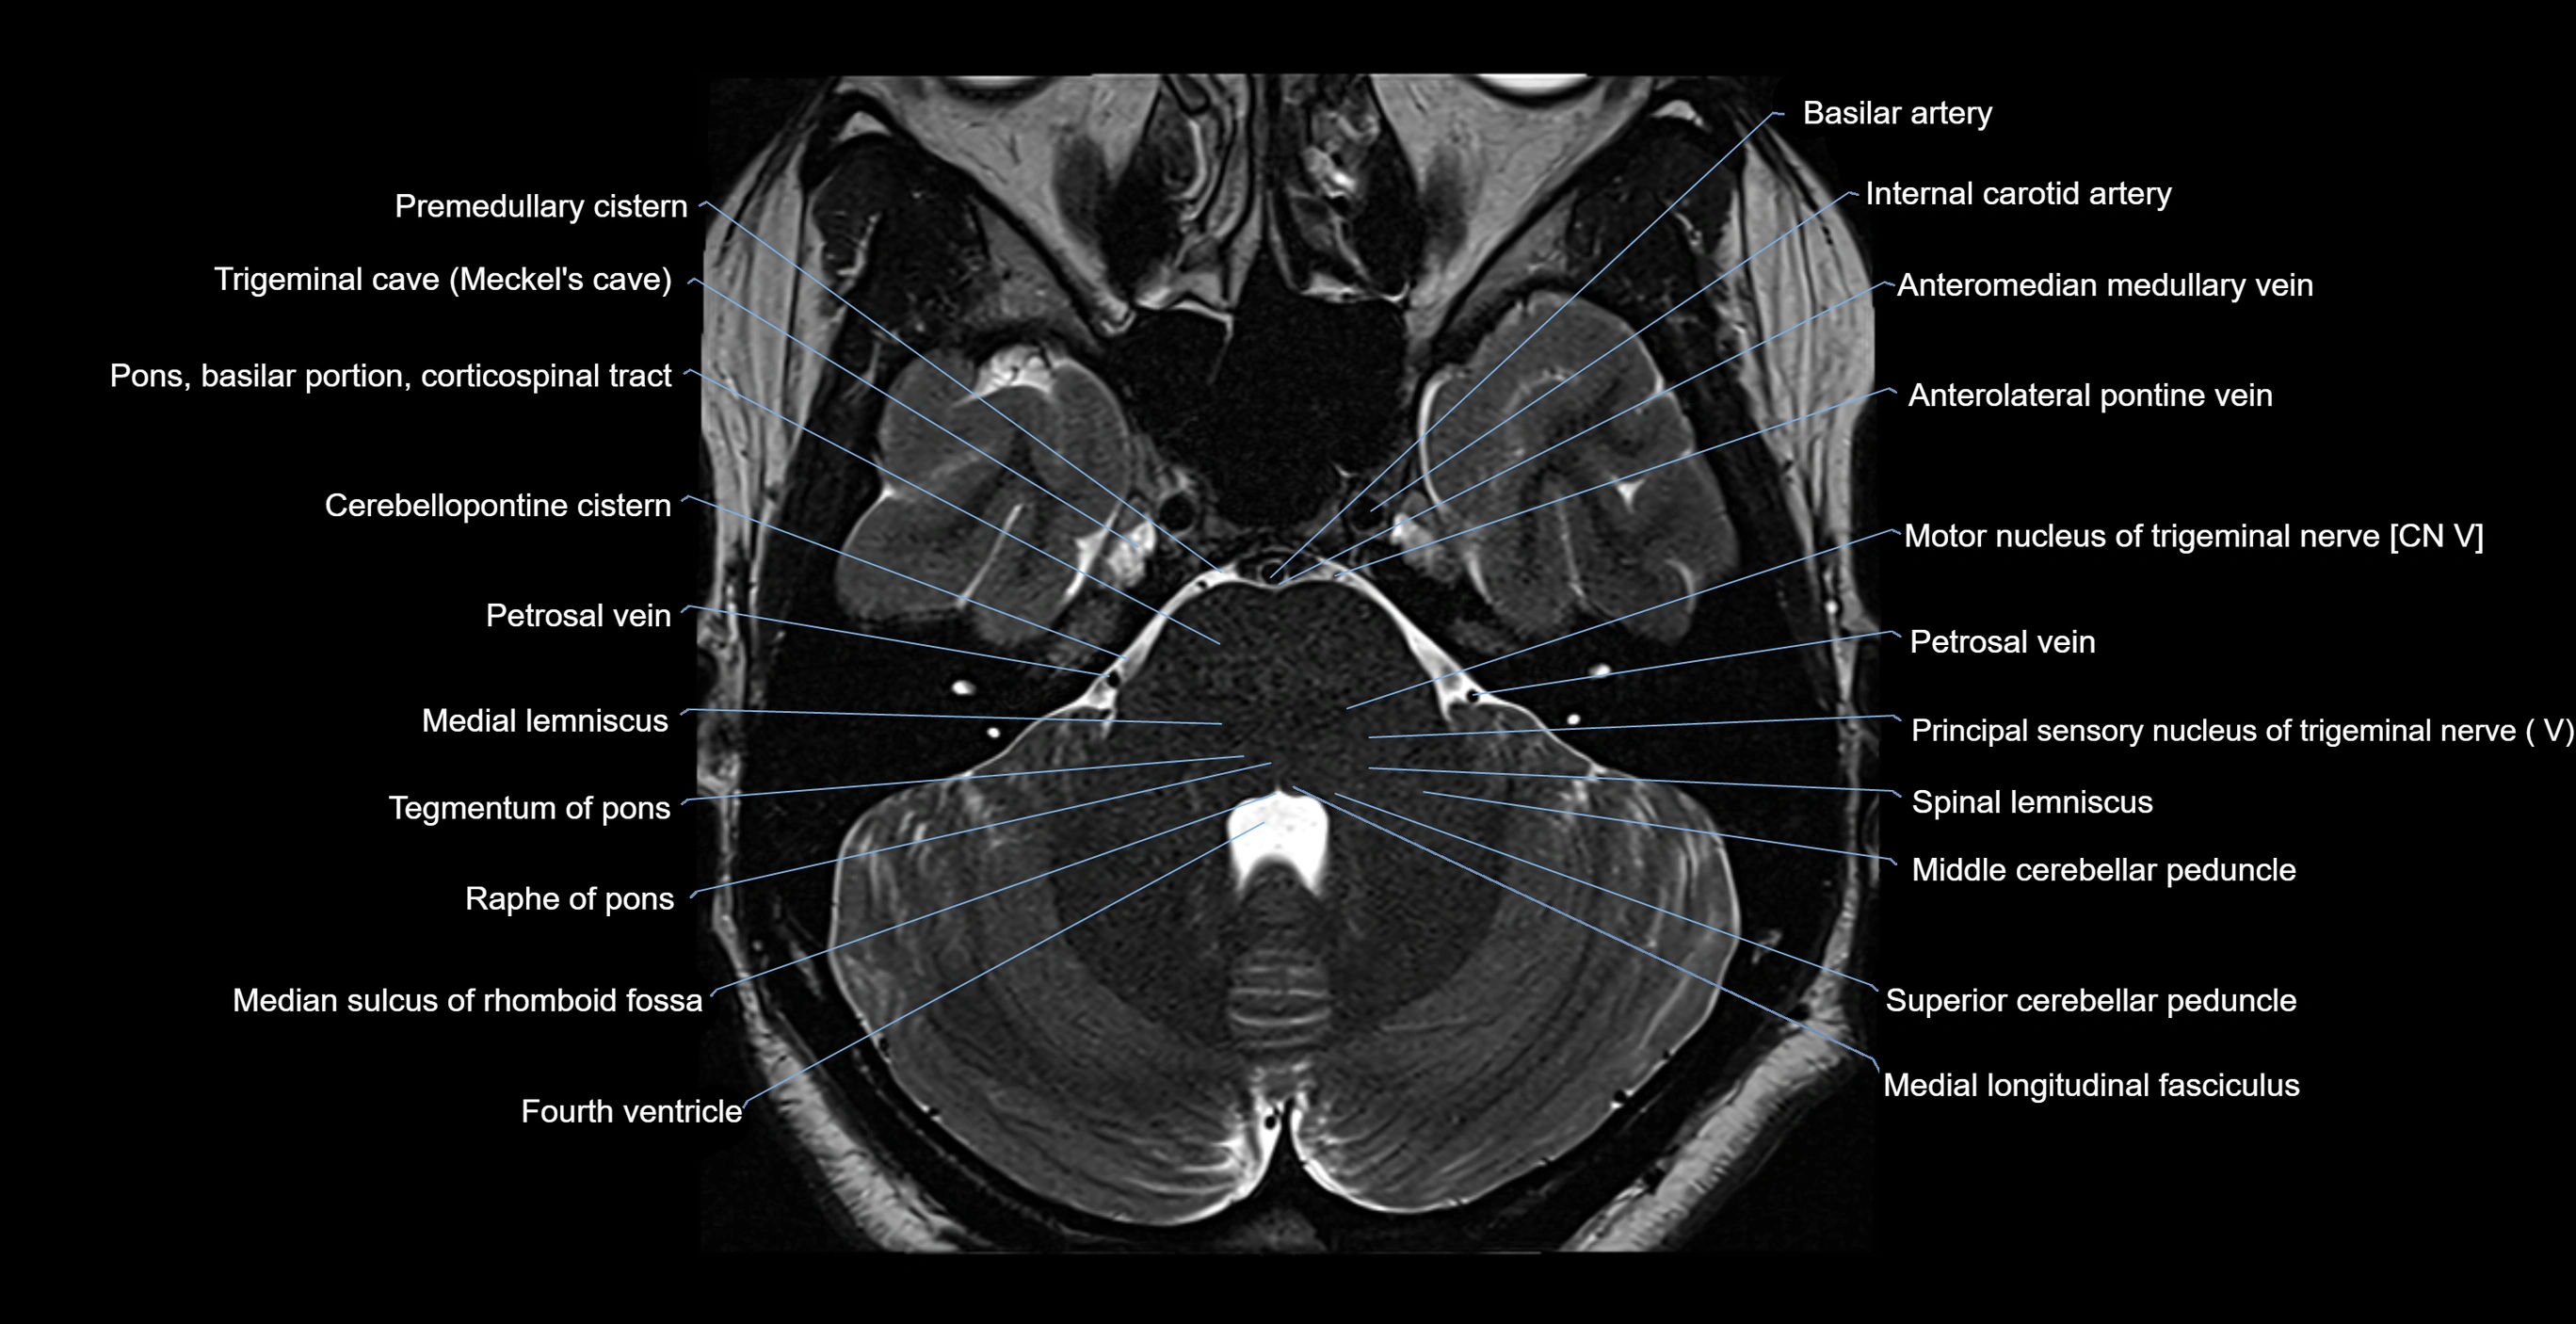

- Anterolateral pontine vein

- Anteromedian medullary vein

- Fourth ventricle

- Medial lemniscus

- Medial longitudinal fasciculus

- Median sulcus of rhomboid fossa

- Middle cerebellar peduncle

- Motor nucleus of trigeminal nerve

- Petrosal vein

- Pons (basilar portion)

- Pontine nucleus

- Principal sensory nucleus of the trigeminal nerve

- Principal sensory nucleus of trigeminal nerve

- Raphe of pons

- Spinal lemniscus

- Superior cerebellar peduncle

- Tegmentum of pons